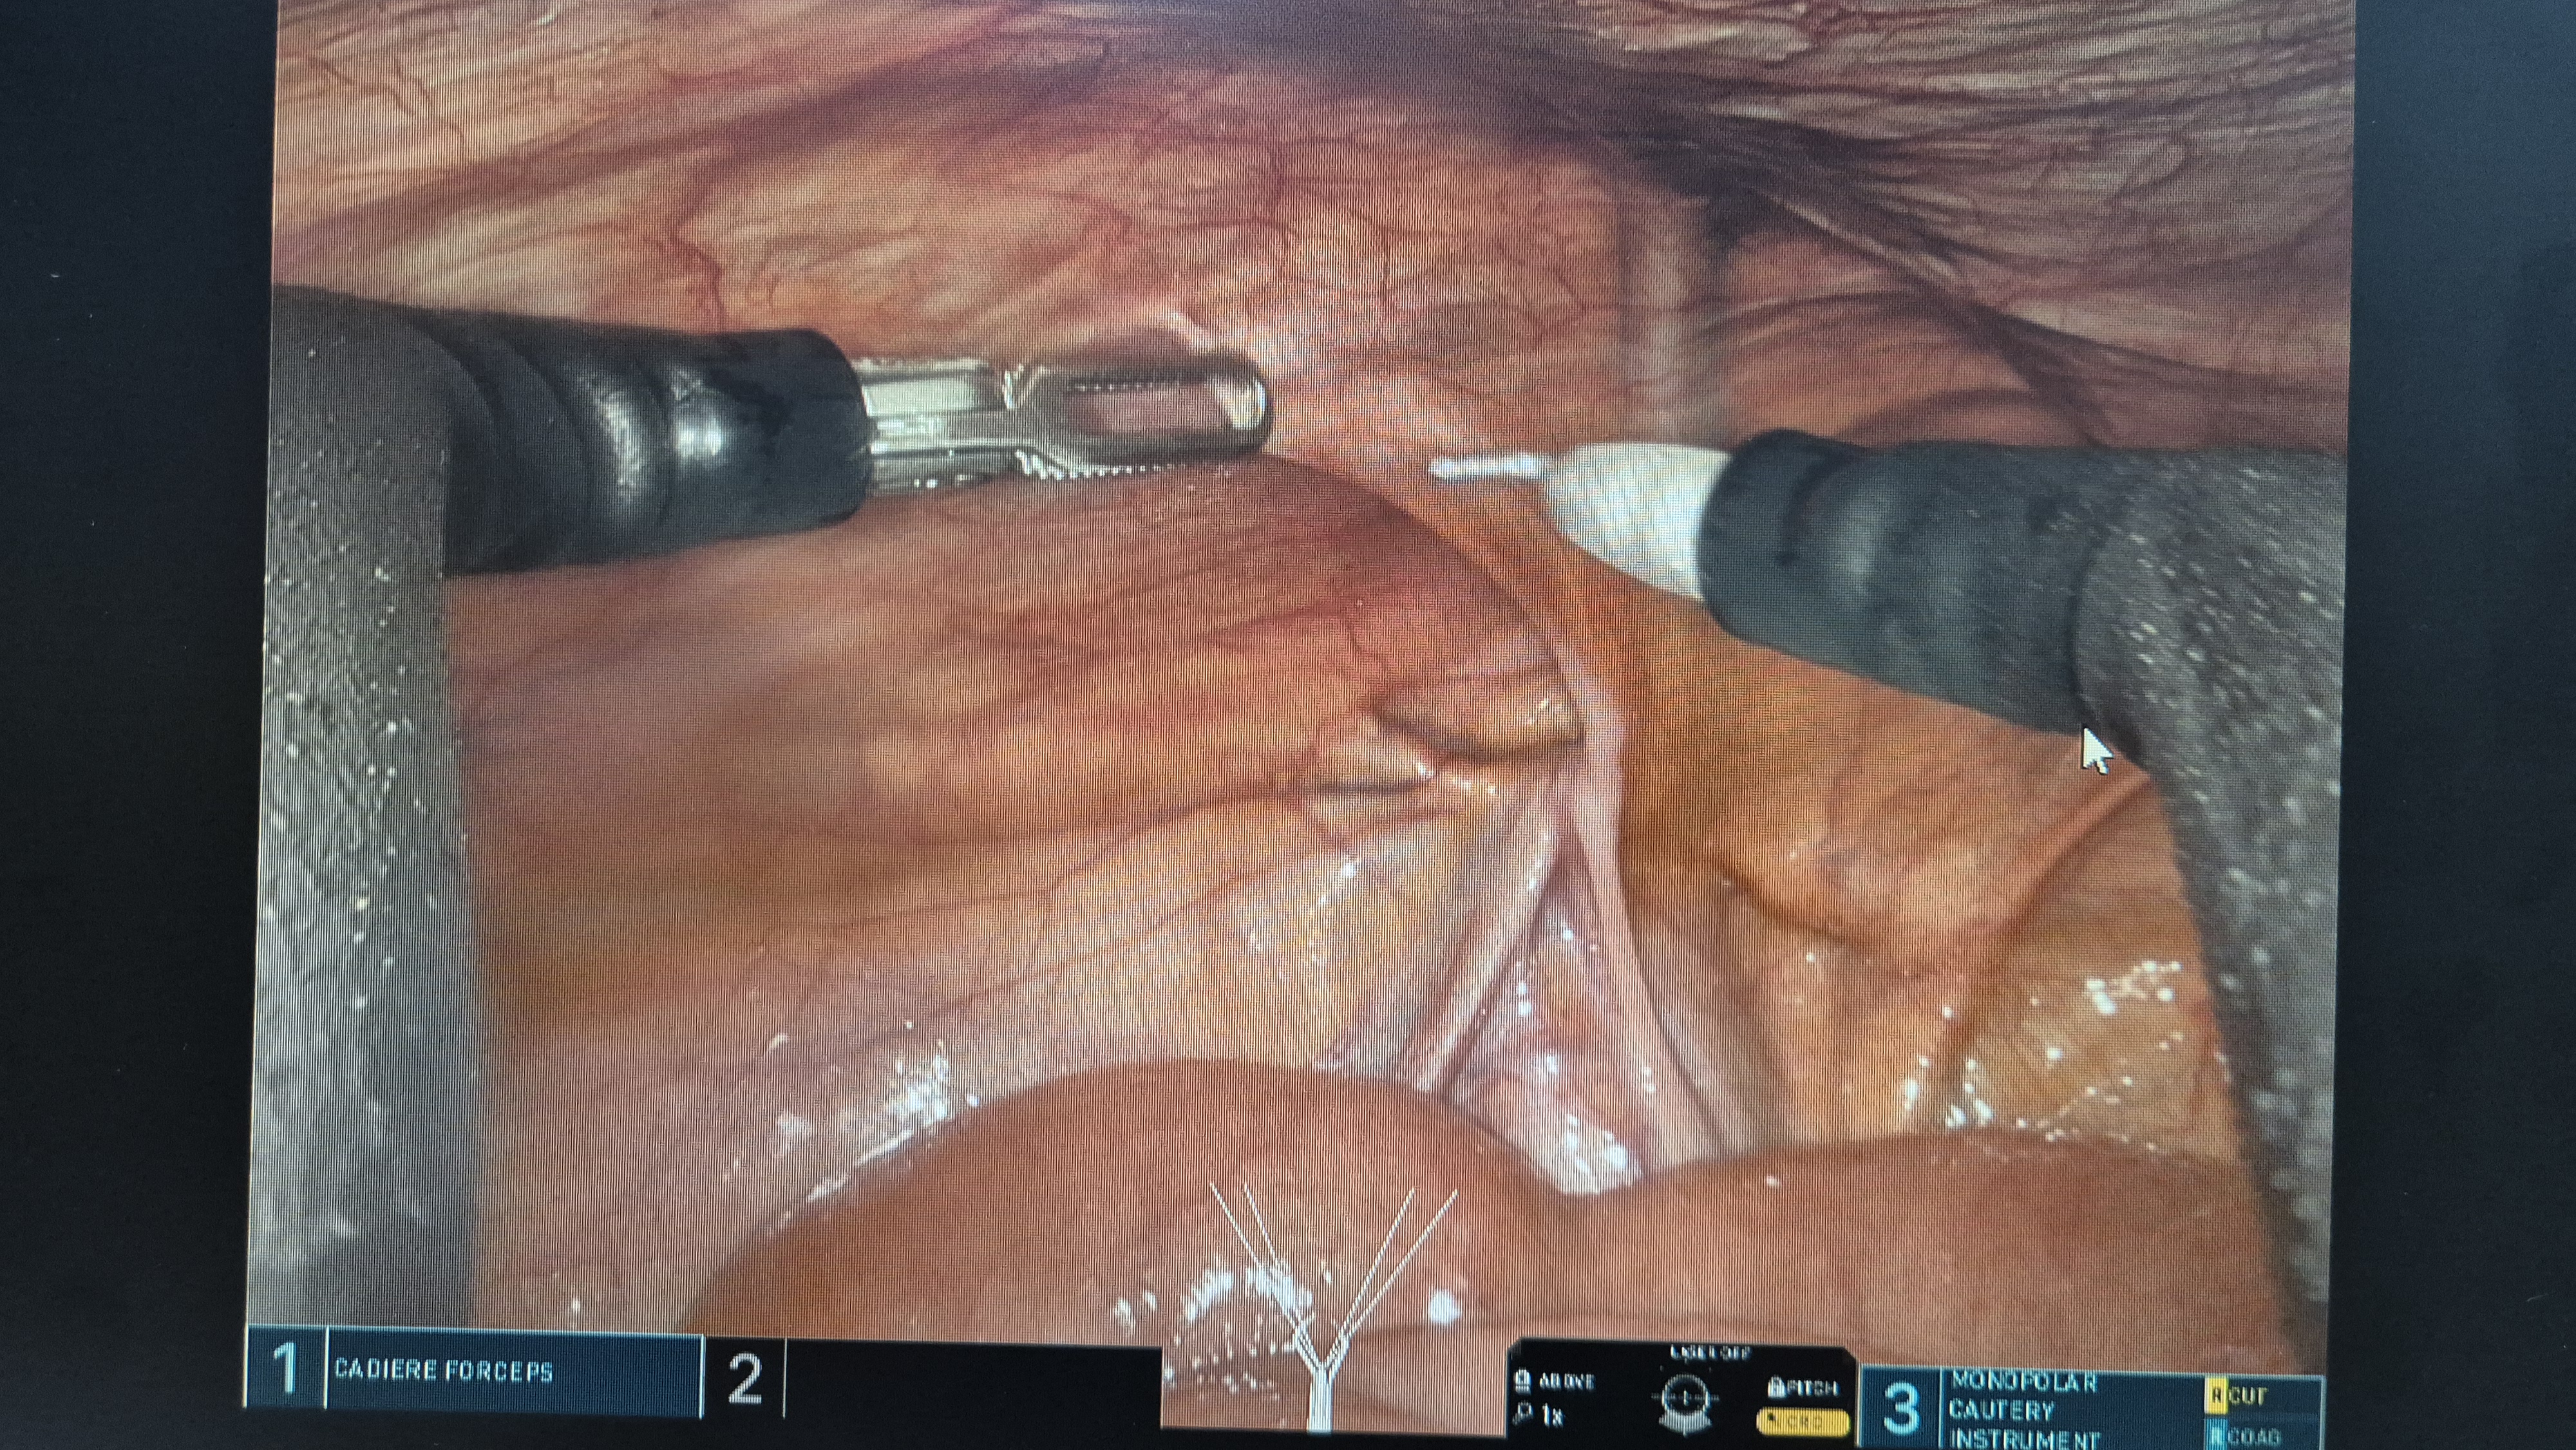

좌측 서혜부 탈장.

복막을 열고.